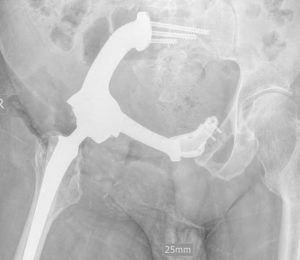

Це історія, яку неможливо забути. Молодий чоловік. Велика пухлина тазової кістки. Складна локалізація, високий ризик та мінімум шансів на просте рішення. Було проведено складну операцію – радикальне видалення пухлини з реконструкцією тазу за допомогою індивідуального 3D-друкованого імпланта. Це був шанс зберегти рух та якість життя. Через 10 місяців виникло інфікування. Довелося видалити імплант разом із кінцівкою. Але ця історія не про поразку. Пацієнт повернувся до активного життя, керує автомобілем і зараз проходить підготовку до екзопротезування. Онкохірургія – це не завжди про ідеальний сценарій, але завжди про можливість вибороти життя і рухатись далі.